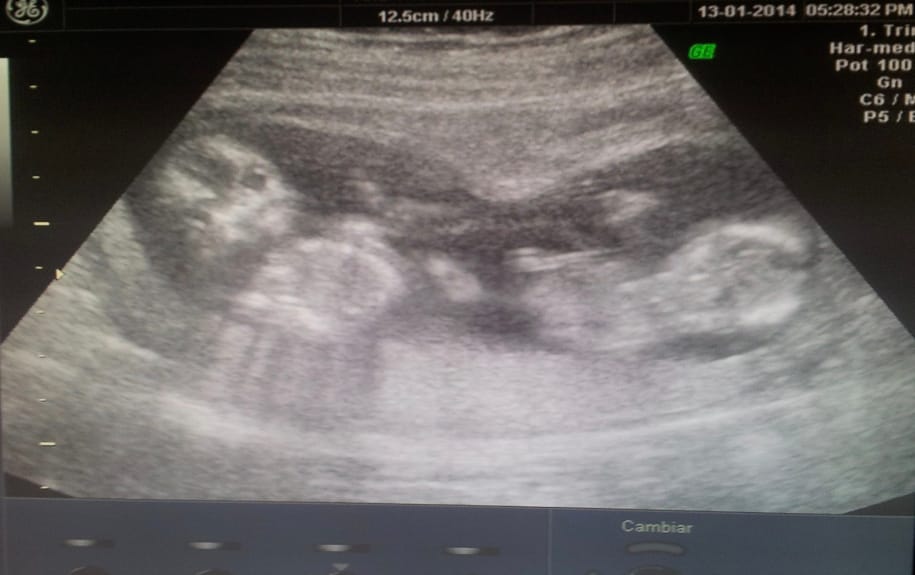

Recuerdo ese instante como si fuera ayer. En el consultorio, el radiólogo me hacía un ultrasonido. Su rostro, concentrado, comenzó a llenarse de preguntas que hicieron que mi corazón latiera con fuerza: «¿Se hicieron algún tratamiento de fertilidad? ¿Hay antecedentes de embarazos múltiples en su familia?» La respuesta me dejó sin aliento: ¡eran gemelas!

Nunca lo imaginé, ni siquiera en sueños. No había tratamientos ni antecedentes familiares. Fue un giro inesperado que transformó mi vida y mi forma de ver el mundo.